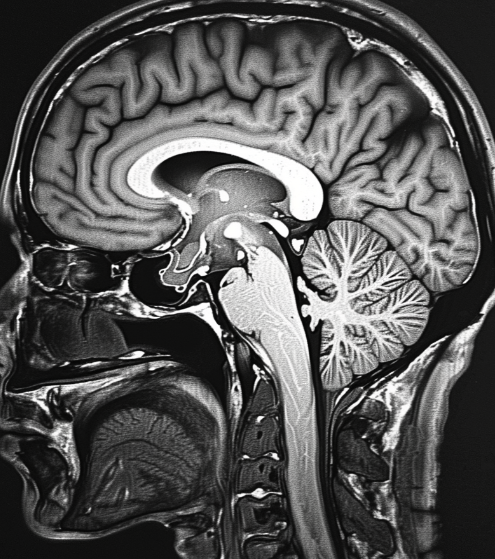

뇌경색은 뇌로 가는 혈류가 갑자기 차단되면서 발생하는 뇌졸중의 한 형태입니다. 이 상태는 뇌 조직에 산소와 필수 영양소가 제공되지 못하게 하여 신경 세포가 손상되거나 죽게 만듭니다. 전조 증상을 조기에 인지하는 것은 중요한데, 이는 적절한 시간 내에 치료를 시작하여 뇌 손상을 최소화하고 회복 가능성을 높일 수 있기 때문입니다. 여기에 몇 가지 중요한 전조 증상들을 나열해 보겠습니다.

뇌경색은 매우 심각한 의료 상황으로, 뇌로 향하는 혈액 공급이 차단되었을 때 발생합니다. 이 상태는 주로 혈전(혈액 덩어리)이 혈관을 막아 발생하며, 이로 인해 뇌 조직이 산소와 영양소를 받지 못하고 손상되거나 죽게 됩니다. 뇌경색은 크게 두 가지 유형으로 나눌 수 있습니다.

- 허혈성 뇌경색: 혈액 공급이 막히는 주된 형태로, 혈관 내에 혈전이 생겨 뇌의 특정 부분으로의 혈액 흐름을 차단합니다. 이는 전체 뇌졸중 사례의 약 87%를 차지합니다.

- 출혈성 뇌경색: 뇌 내부의 혈관이 파열되어 출혈이 발생하는 상황입니다. 이 경우에는 뇌 내압이 증가하며, 주변 뇌 조직에 추가적인 손상을 초래할 수 있습니다.